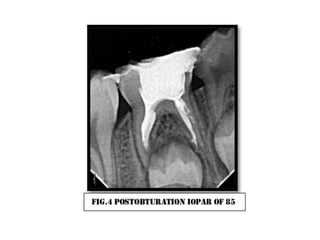

Pulpectomy with ss crown case 3 PPTX

Pulpectomy with ss crown case 2 PPTX

Pulpectomy with ss crown case 1 PPTX